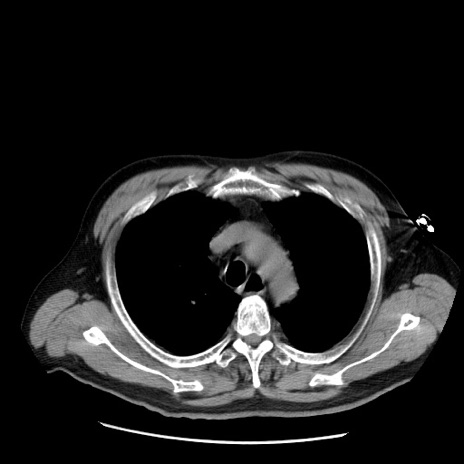

症例20(横断像)

【症例】 60歳代男性

【主訴】 腹部膨満、嘔吐

【現病歴】5日前頃より倦怠感を認め食事量減少し4日前の朝嘔吐、食事摂取困難となった。 3日前近医受診し点滴施行され整腸剤などを処方された。 当日他院を受診し、腹部膨満著明、炎症反応の上昇(CRP10.8、WBC11200)あり、紹介受診となる。

【身体所見】 意識JCS1 受け答えがはっきりしないBP 111/57mHg、 P 67bpm、、BT35.2°C、SpO2 97%(RA)、 腹部:膨隆、打診で鼓音あり、全体的に圧痛有り、腸蠕動音(-)、反跳痛ははっきりせず。

【データ】WBC 11400、CRP 14.20